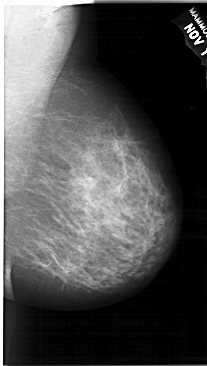

A_1691_1.RIGHT_CC

RIGHT_MLO LINES 6586 PIXELS_PER_LINE 3721 BITS_PER_PIXEL 12 RESOLUTION 43.5 NON_OVERLAY